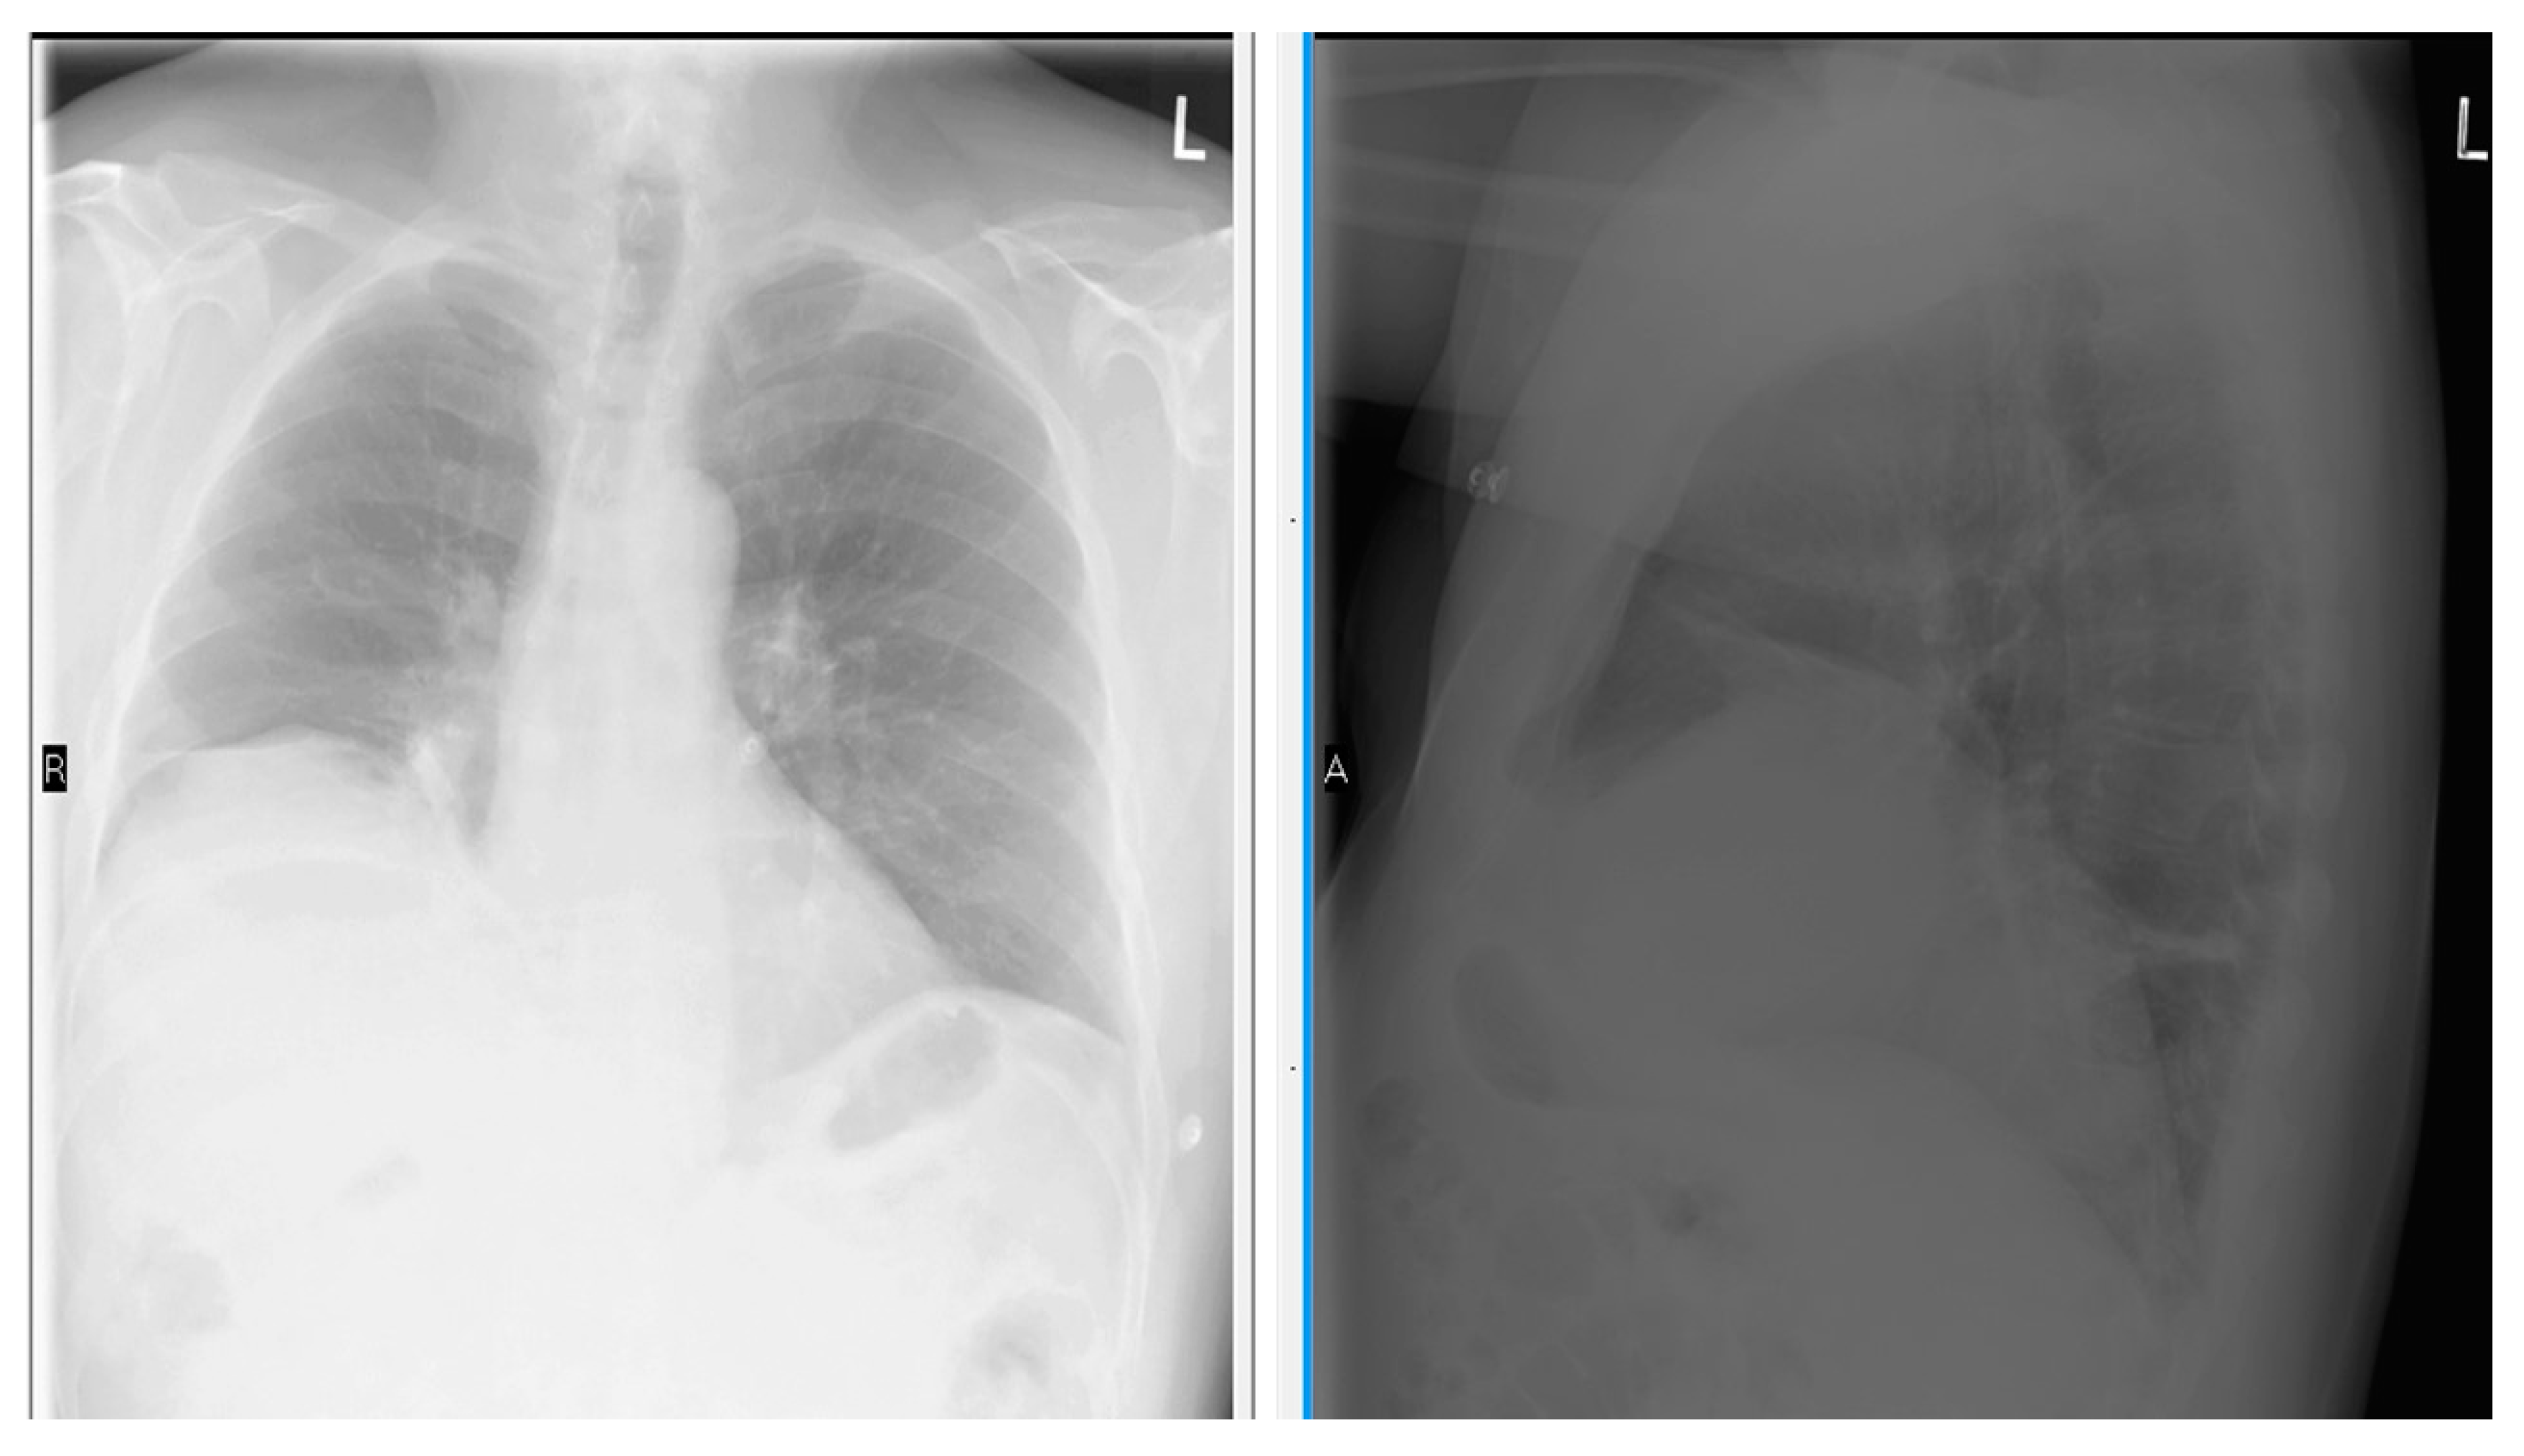

- Chetta, A.; Rehman, A.K.; Moxham, J.; Carr, D.H.; Polkey, M.I. Chest radiography cannot predict diaphragm function. Respir. Med. 2005, 99, 39–44. [Google Scholar] [CrossRef] [PubMed]

- Nason, L.K.; Walker, C.M.; McNeeley, M.F.; Burivong, W.; Fligner, C.L.; Godwin, J.D. Imaging of the diaphragm: Anatomy and function. Radiographics 2012, 32, E51–E70. [Google Scholar] [CrossRef] [PubMed]